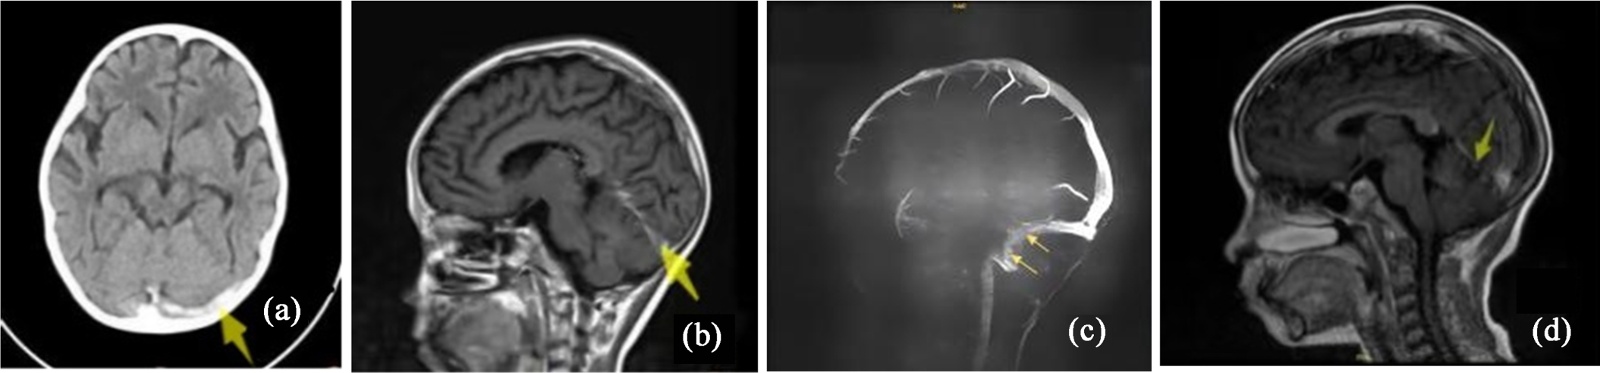

患者,男,10岁,因“发热4天”入院。依据骨髓MICM结果诊为急性淋巴细胞白血病(B系,中危)。入院时颅脑MR未见异常,血凝常规无异常,按CCCG-ALL2020方案予VDLD诱导缓解治疗。治疗第33天,患儿诉头痛,行颅脑CT示双侧横窦、直窦、双侧大脑大静脉、大脑内静脉密度增高(如图2(a))。脑增强MR示左乙状窦、左横窦、直窦静脉血栓形成(如图2(b))。脑静脉MR血管成像(MRV):左乙状窦、左横窦、直窦显影浅淡(如图2(c))。血常规正常,血凝常规:PT 13 s,APTT 34.6 s,FIB 0.44 g/L,AT-III 63%,DD 870 ng/mL。予低分子肝素抗凝治疗17天,后换用利伐沙班口服,抗凝治疗3月复查颅脑增强MR示左侧横窦充盈缺损不明显(如图2(d))。患儿后续使用PEG-Asp方案化疗5次均未再有血栓形成。动态复查颅脑MR至抗凝治疗10月,血栓未反复,停用利伐沙班。

(a) 治疗前脑CT;(b) 治疗前脑增强MR;(c) 治疗前脑MRV;(d) 治疗3月后脑增强MR。

Figure 2. Comparative cranial imaging of case 2: Pre-treatment vs post-treatment

2. 病例2治疗前后颅脑影像变化